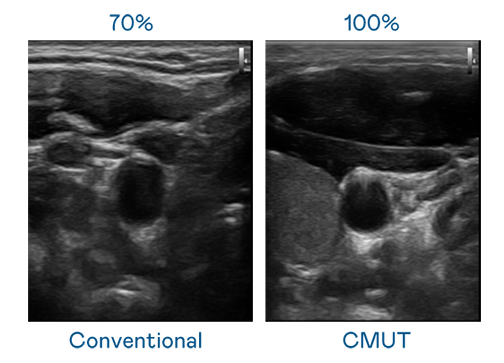

CMUT 技術是一種用電容式微機電元件來產生超音波訊號的技術。與傳統 PZT 壓電式技術相比,CMUT 頻寬增加 30%,更寬頻的超音波訊號讓影像解析度大幅提升,是實現高影像品質醫療超音波掃描、促進精準醫療發展的關鍵技術。

超音波影像的解析度高低,首先取決於探頭能發出的訊號頻寬。冰球突破 CMUT 可提供高清晰的超音波訊號,提供高頻寬、高靈敏度、影像紋理細節更高的超音波影像,協助醫護人員縮短影像判讀時間及利用精準的醫療影像進行診斷。